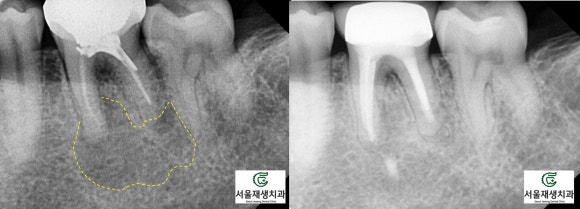

한 눈에 보기에도 병소의 크기가 꽤나 크지요?

치아가 뿌리 끝에 자기 몸뚱이만큼이나 큰 물혹을 달고 있습니다.

<병소가 큰 재신경치료 케이스의 비포 애프터>

(9개월 소요)

(8개월 소요)

(6개월 소요)